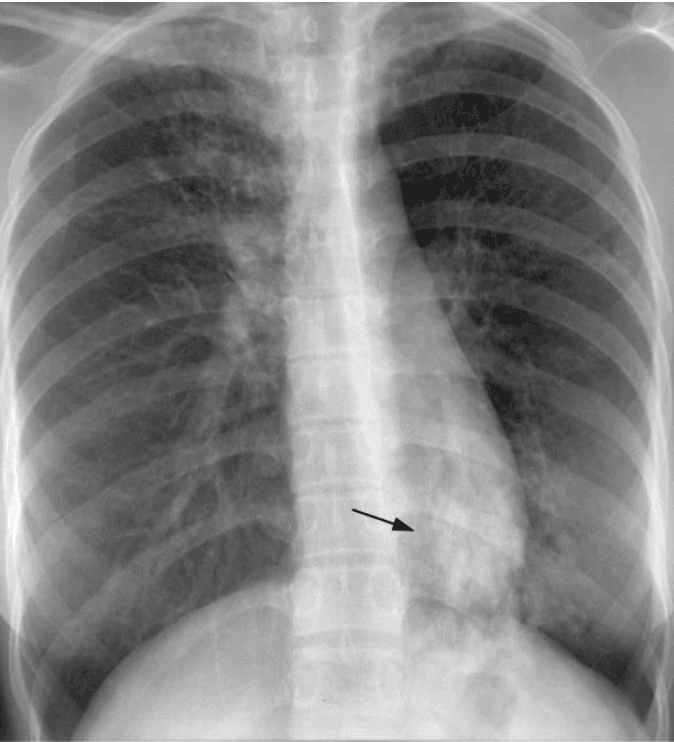

Chest X-rays can reveal abnormalities in the lungs suggestive of TB, such as cavities, consolidations, or infiltrates. While not specific for TB, chest X-rays are often used as an initial screening tool and to monitor disease progression or response to treatment.